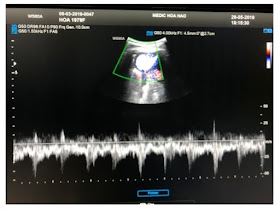

ULTRASOUND OF THE NECK   DETECTED R CCA OBSTRUCTION  COMPLETELY BUT R/ECA STILL HAD FLOW.

US1, US2, US3 =  R -CERVICAL ARTERY  HAD FLOW UP.